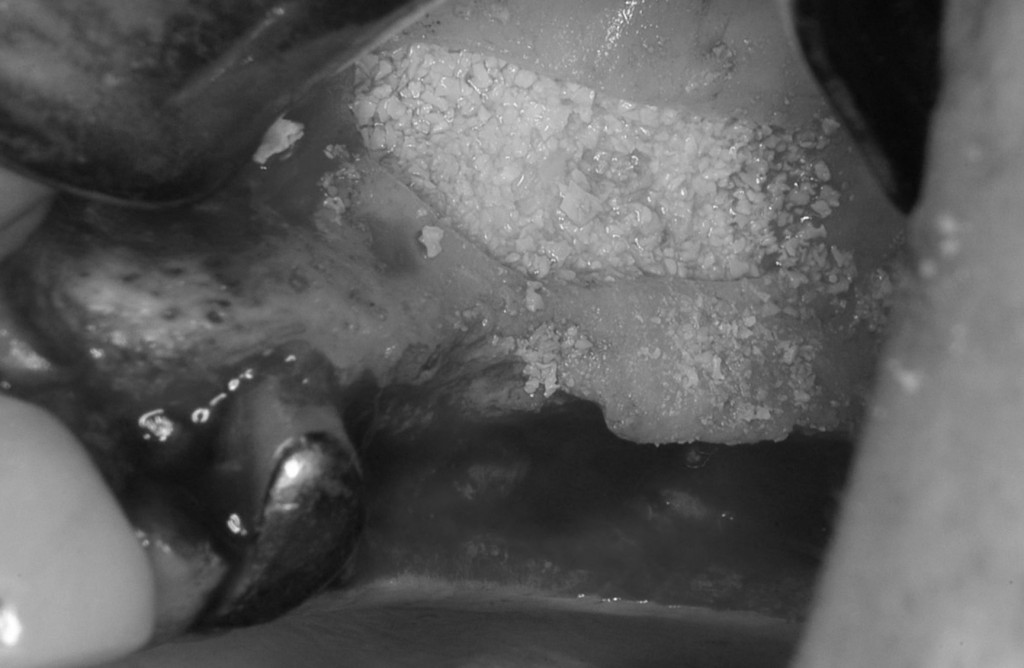

まずはインプラントを支えるための骨を造る必要がありましたので,サイナスリフトという手術を行いました。

上顎骨の空洞に骨を造る手術で,一般的な歯科医院では行うことが出来ない,高度な技術が必要な手術です。ひと昔前では,大学病院で入院して行うような手術でしたが今は材料と医療機器,技術の進歩で,日帰りで手術を行うことが出来ます。